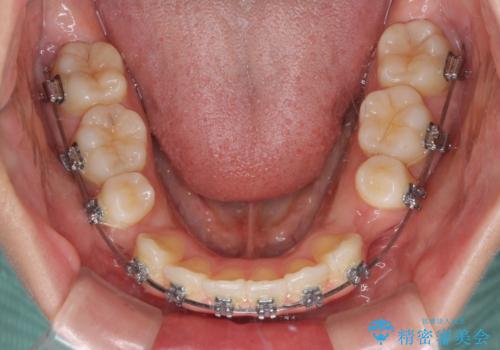

- メタルブラケット

- 1年5ヶ月

上下ともに歯列が前方に突出していたため、上下左右の第一小臼歯4本を抜去し、ワイヤー装置による矯正治療を行うこととしました。

上下左右4本抜歯する場合には、通常2年から2年半ほどの期間を要しますが、僅か1年半で終了することができました。